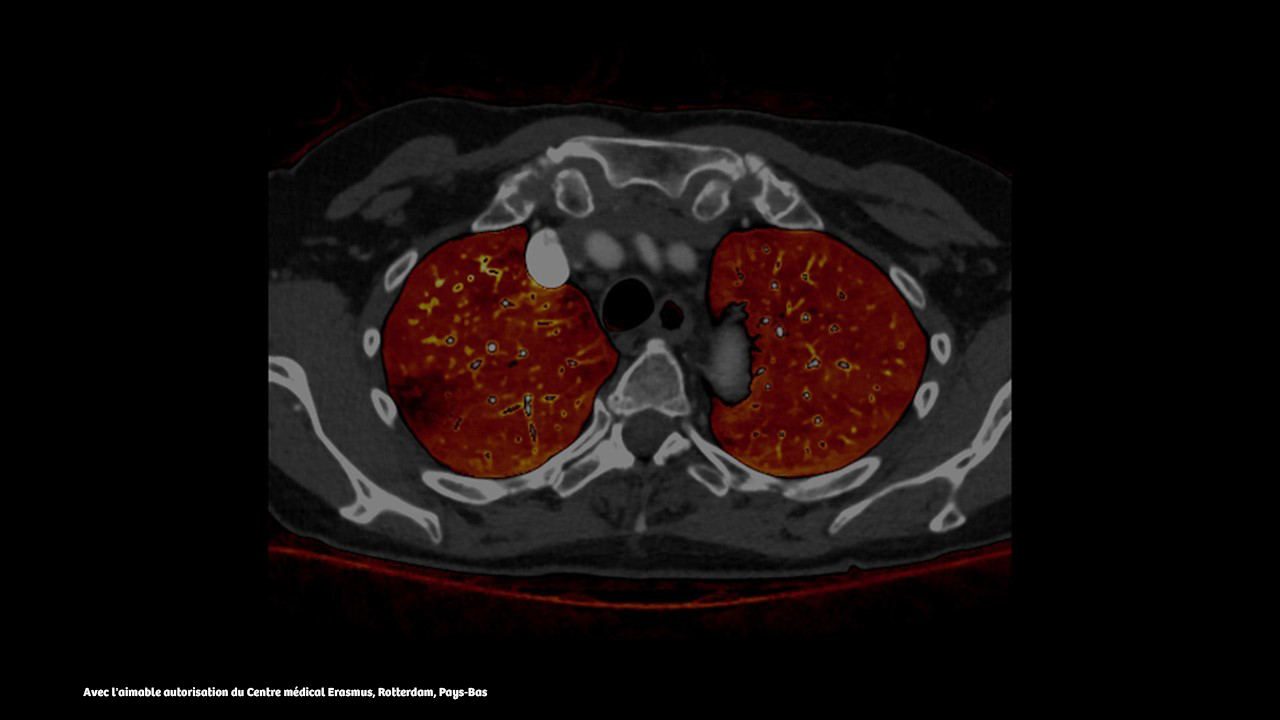

L’examen par scanner à comptage de photons avec vitesse Dual Source offre des capacités cliniques uniques pour les patients difficiles à examiner. Scannez les patients présentant des risques cardiaques sans bêta-bloquants, accélérez l'imagerie pédiatrique et effectuez des balayages en respiration libre pour les patients en pneumologie.

Le NAEOTOM Alpha.Pro offre une acquisition à pitch élevé et des informations spectrales à n'importe quelle vitesse d'acquisition, ce qui facilite le flux de travail et facilite le diagnostic. Les cartes de perfusion et d'iode contribuent à un diagnostic précis en oncologie et dans les évaluations des accidents vasculaires cérébraux.